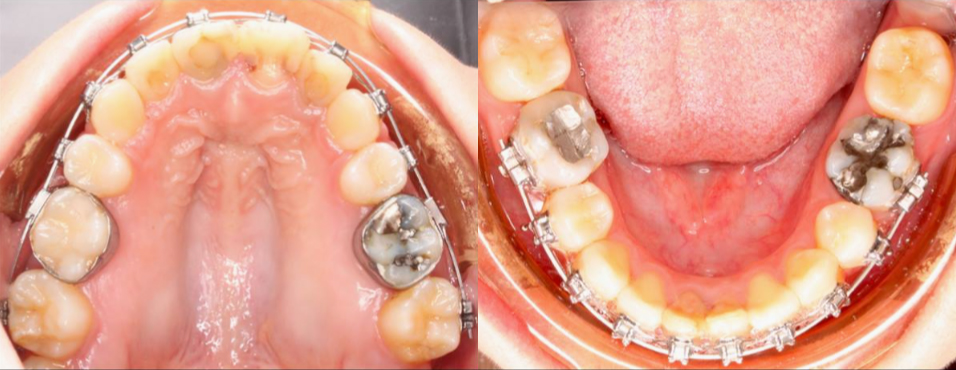

治療前

治療中